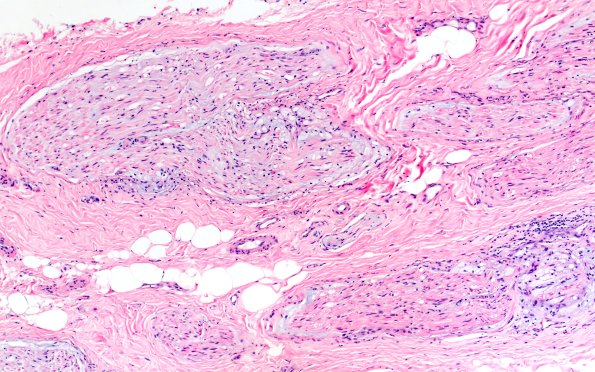

Washington University Experience | PERIPHERAL NEUROPATHY | 21 PRIMARY BILIARY CHOLANGITIS NEUROPATHY | 1A2 Primary Biliary Cirrhosis (Case 1) H&E 10X 1

1A2-4 At higher magnification the perineurium appears expanded and foamy. (H&E)